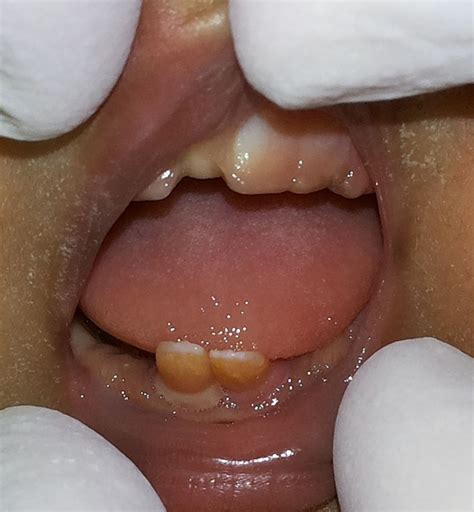

Natal teeth are teeth that are present at birth or appear within the first 30 days of a newborn's life. They are different from neonatal teeth, which erupt between one and three months of age. Natal teeth are often the lower central incisors, but they can also be the upper incisors or even molars. These teeth can be fully developed or partially erupted, and they may be loose or firmly attached to the gum.

• babies born with teeth pictures